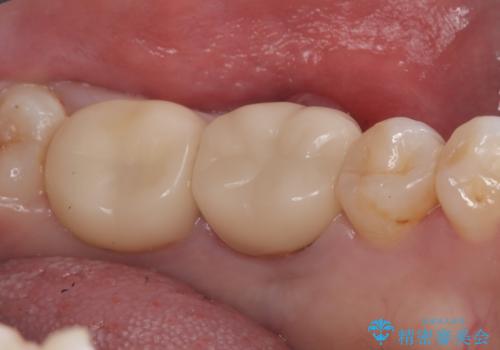

骨との定着を確認し、今後矯正治療を行う予定のためレジン冠をセットしています。